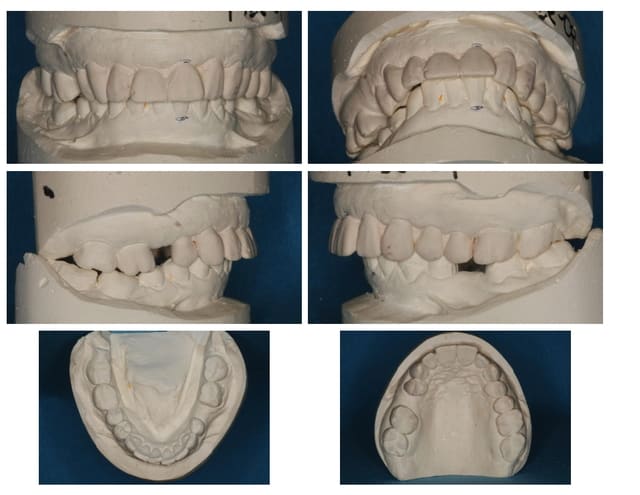

Suite du p'tit cas de ré-hab.

Cirage (wax-up en français ;-))

Gain en vertical et en AP (antéro-postérieur)

Disparition de la Cl-2 par callage postérieur et repositionnement mandibulaire.

Alors, non, tu as faux...

Comment corriger physiologiquement un écart antéro-postérieur, une DV antérieur et postérieur, en relevant de façon subjective une tige sur un articulateur, qui malgré son nom, n'est qu'une penture.

Regarde bien le cirage/wax-up vue de côté.

J'ai ouvert plus en postérieur, qu'en antérieur, et plus d'un côté que de l'autre, et modifié la position antéro-postérieure. J'ai travaillé sur plusieurs axes (d'où l'inutilité de bouger la tige de l'articulateur).

Regarde bien le wax-up.